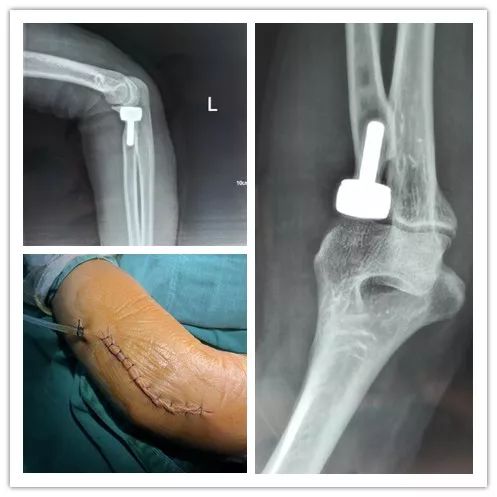

云南省第一人民医院骨科成功实施左桡骨

知否?知否?一个病例教您识左桡骨小头骨折